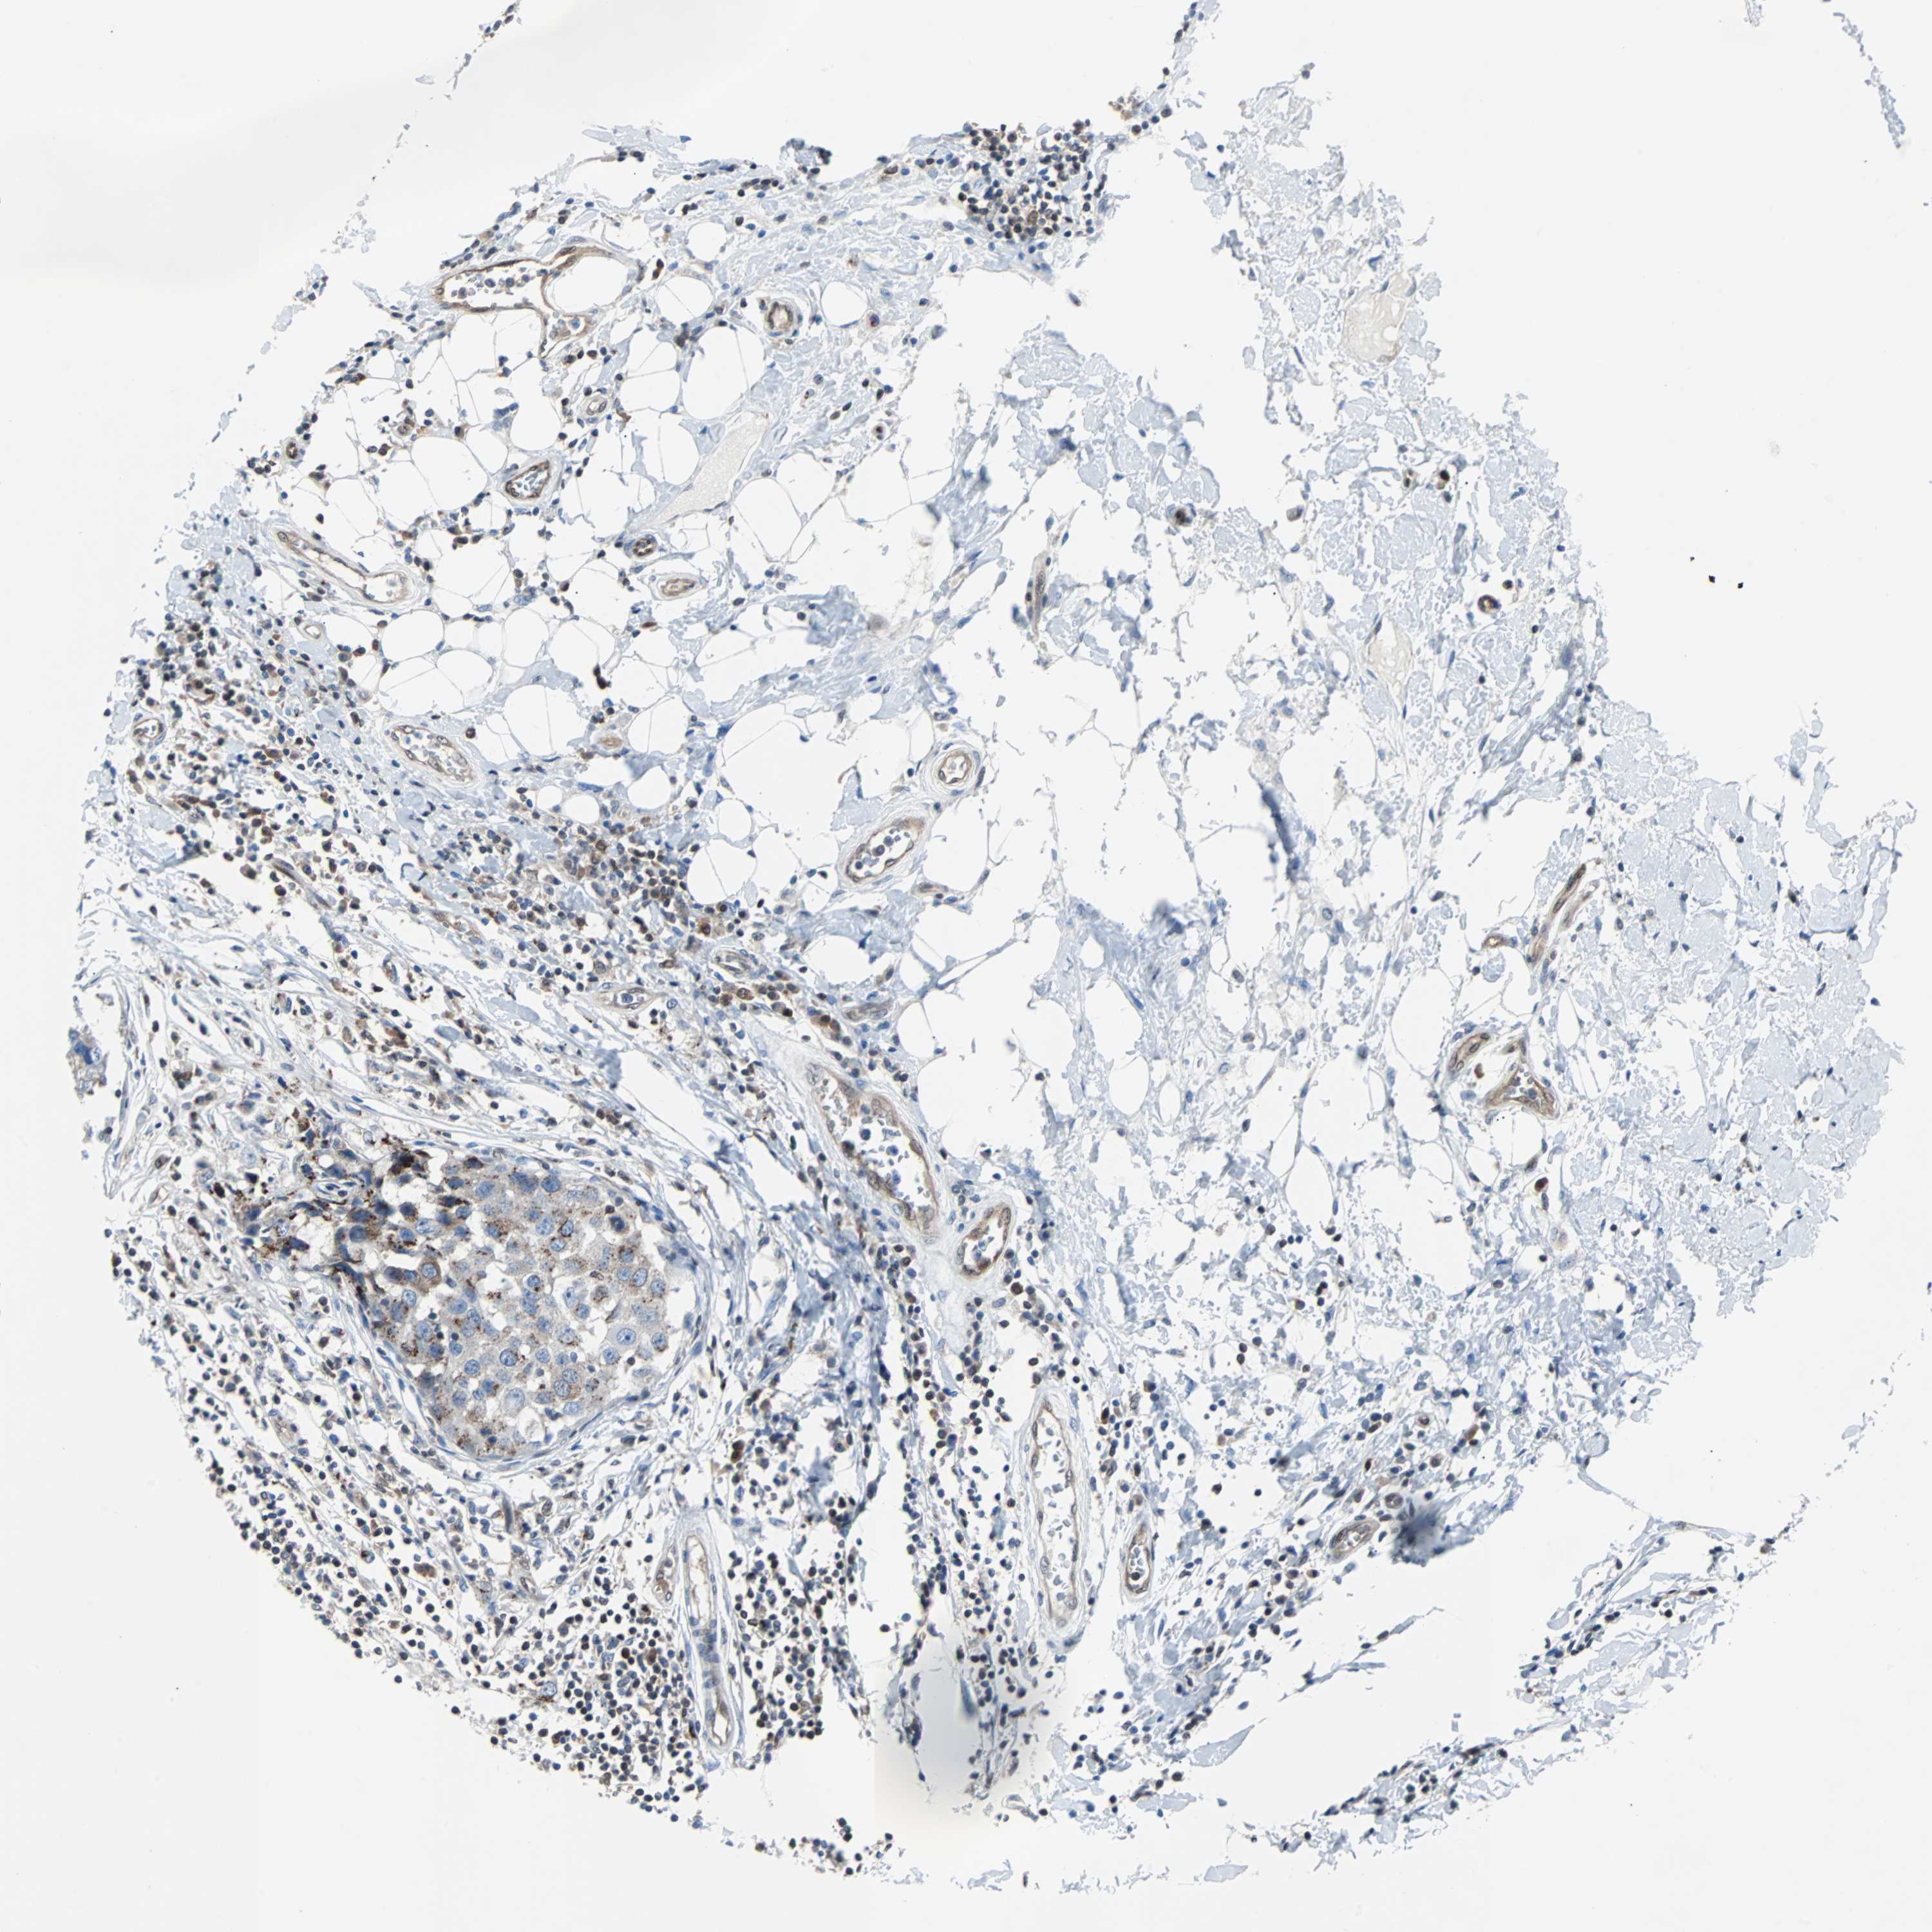

CANCER BREAST CANCER Show tissue menu

BRCA TCGA BRCA VALIDATION PROTEIN EXPRESSION

Breast cancer

Human cancer

MAP2K6 is potential prognostic, high expression is favorable in Breast Invasive Carcinoma (TCGA)